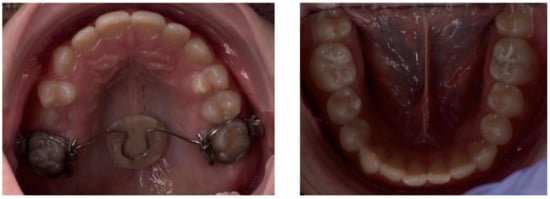

2.3.2. Second Phase of Treatment—2017—Bite-Blocks and Transpalatal Arch